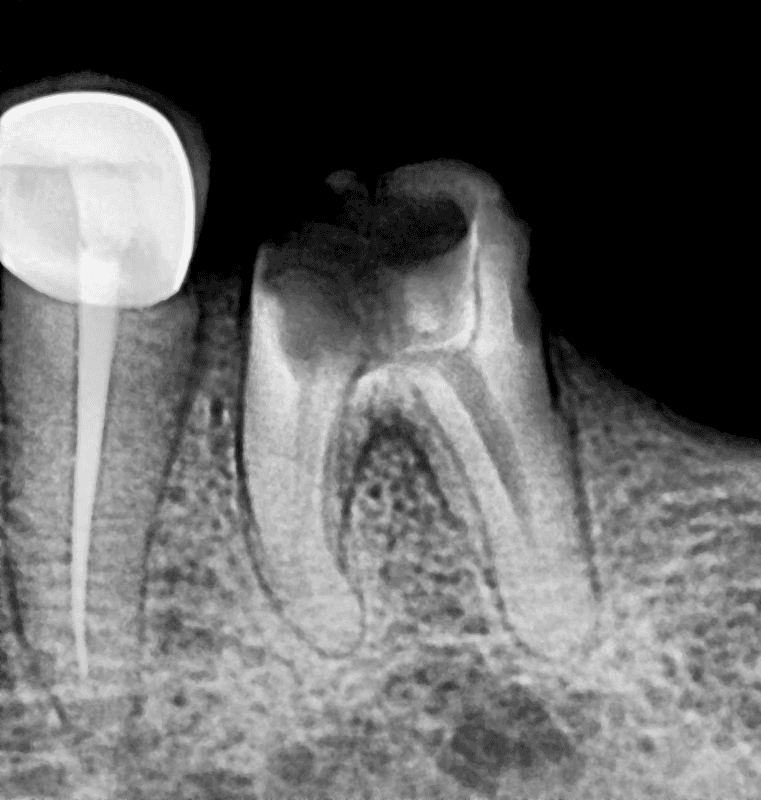

Before

After

Lower Molar

Severe Infection

Lower Molar Root Canal

Infection in the lower molar causing intense pain and swelling. Root canal treatment was performed to save the tooth.

Severe infection eliminated

Pain relief within 24 hours

Natural tooth saved